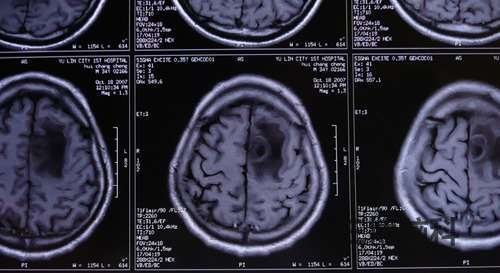

患者尹某,男,34岁。头痛、频发抽搐。MRI:左额顶近中先驱灶状占位,周围水肿明显。诊断:脑脓肿。立体定向微创技术切除病变。恢复良好。附图显示手术前后MRI比较。

术后显示:脑脓肿完全切除,患者症状消失,恢复良好。